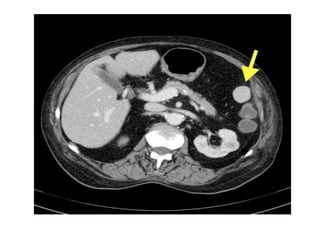

CT grading of splenic rupture.

• In it splenic lacerations appears as linear low

attenuation defects that contrast well with

high attenuation vascular spleen.

• Intra splenic hematomas appear as more

diffuse hypo-attenuating region with irregular

margins with splenic swelling.

• Uniform enhancement occurs approximately 50-60

seconds after contrast administration, so imaging

during early arterial phase is useful in detection of

active extravasation and for pseudo-aneurysms.